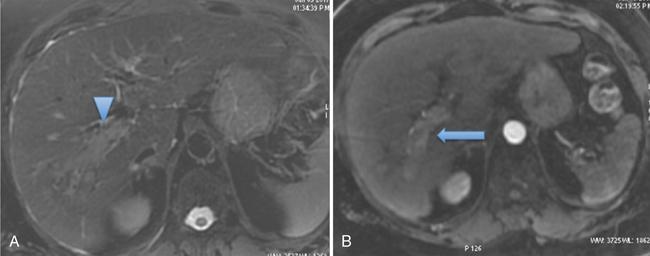

HCC is the commonest primary malignant tumour seen in the cirrhotic patients and hence screening for HCC is regularly performed in these patients. Presence of HCC does not preclude transplantation, and in fact, it is one of the indications for liver transplants. Liver transplantation serves as the best treatment for early-stage HCC, as it not only treats the tumour but also the underlying liver disease (the main risk factor for the development of new tumours). However, careful selection of the patients is essential to achieve best and curative results in these patients and avoid early recurrence.

All the major criteria for liver transplant take into account the number and size of the HCCs and hence is important to assess in detail. Any major vascular invasion or tumour thrombus in main and primary branches of the portal vein by tumour and extrahepatic disease are contraindications for liver transplant and hence should be carefully looked for.

Milan’s criteria was proposed in 1996 by Mazzaferro et al. Excellent outcomes are seen after LT in patients fitting with Milan’s criteria. However, strict adherence to Milan’s criteria may deny chance of transplant to patients with slightly more advanced HCC who may still benefit and have acceptable outcomes after transplant. This was the rationale behind the development of the University of California San Francisco (UCSF) criteria (Fig. 9.14.9) which showed recurrence-free survival rate comparable to the Milan criteria at the same time expanding the opportunity of LDLT to more patients.